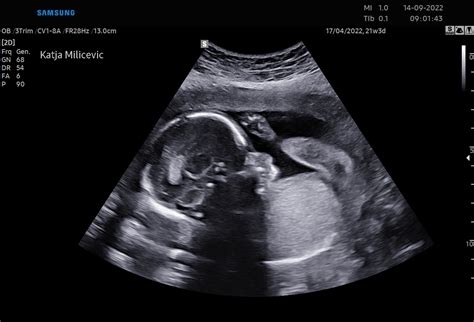

Ultrazvočni pregled v 20. tednu: Podroben vpogled v razvoj

Okoli 20. tedna nosečnosti je običajno načrtovan podroben ultrazvočni pregled, znan kot morfološki ultrazvok. Ta pregled je ključen za oceno pravilnega razvoja ploda. Zdravnik bo natančno preveril vse organe, vključno s srčnimi prekati, možganskimi hemisferami, okončinami in notranjimi organi. Če pričakujete dvojčke, bo zdravnik posebej pozoren na velikost glav obeh plodov.

Na tem pregledu je pogosto možno izvedeti tudi spol otroka. Če si želite to informacijo izvedeti, zdravniku povejte. Prav tako je to odličen čas, da prosite za natisnjeno fotografijo vašega malčka, ki jo boste lahko cenili še dolgo po porodu.